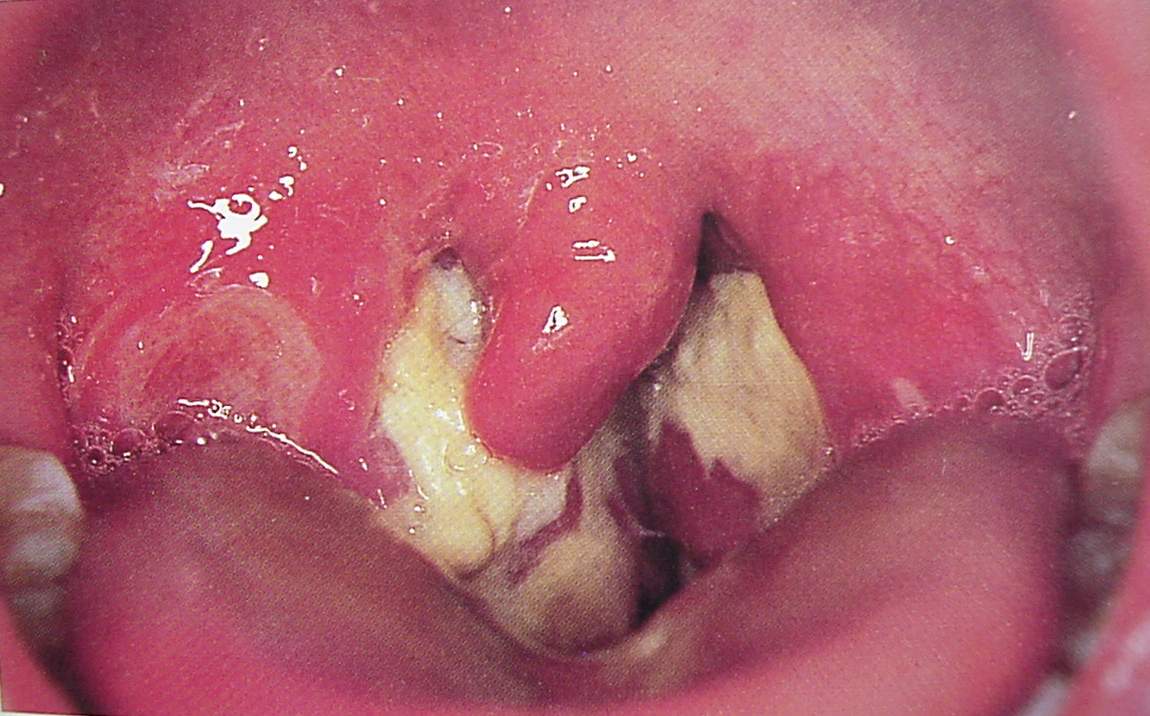

Pharynx and Esophagus Clinical Photos for Static Stations